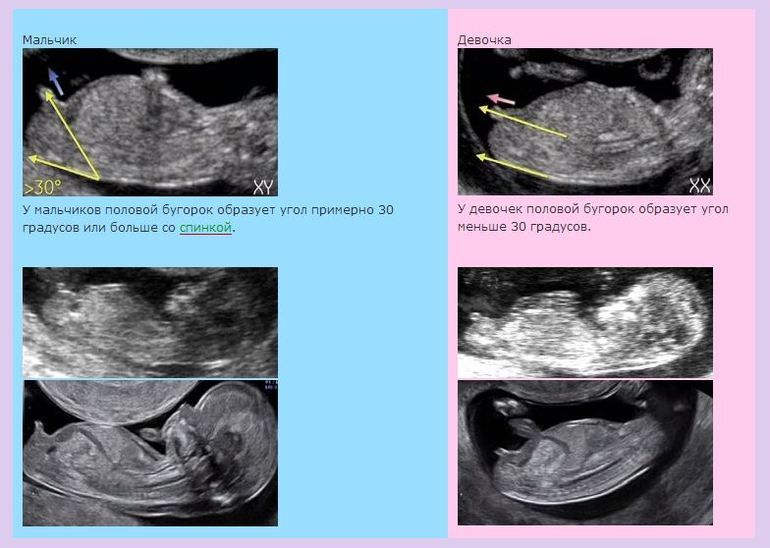

Ничего там не болтается ни у мальчиков (лихо Вы про письку выразились😂), ни у девочек на таком сроке. Есть только половой бугорок, по наклону которого можно предположить, кто получится. Они очень похожи, правда. Смотреть надо в профиль. Изображение Вот так. Могу глянуть, но ничего на 100% не обещаю)) У моего пенис увидели на 15 неделе, например, но дали небольшой процент, что пуповина затесалась в кадре. Потом на 2 скрининге в полных 18 недель уже точно всё разглядели.

Половой бугорок - это то, что станет половым органом. Половой покой - значит покой, ничего нельзя, тем более испытывать оргазм.